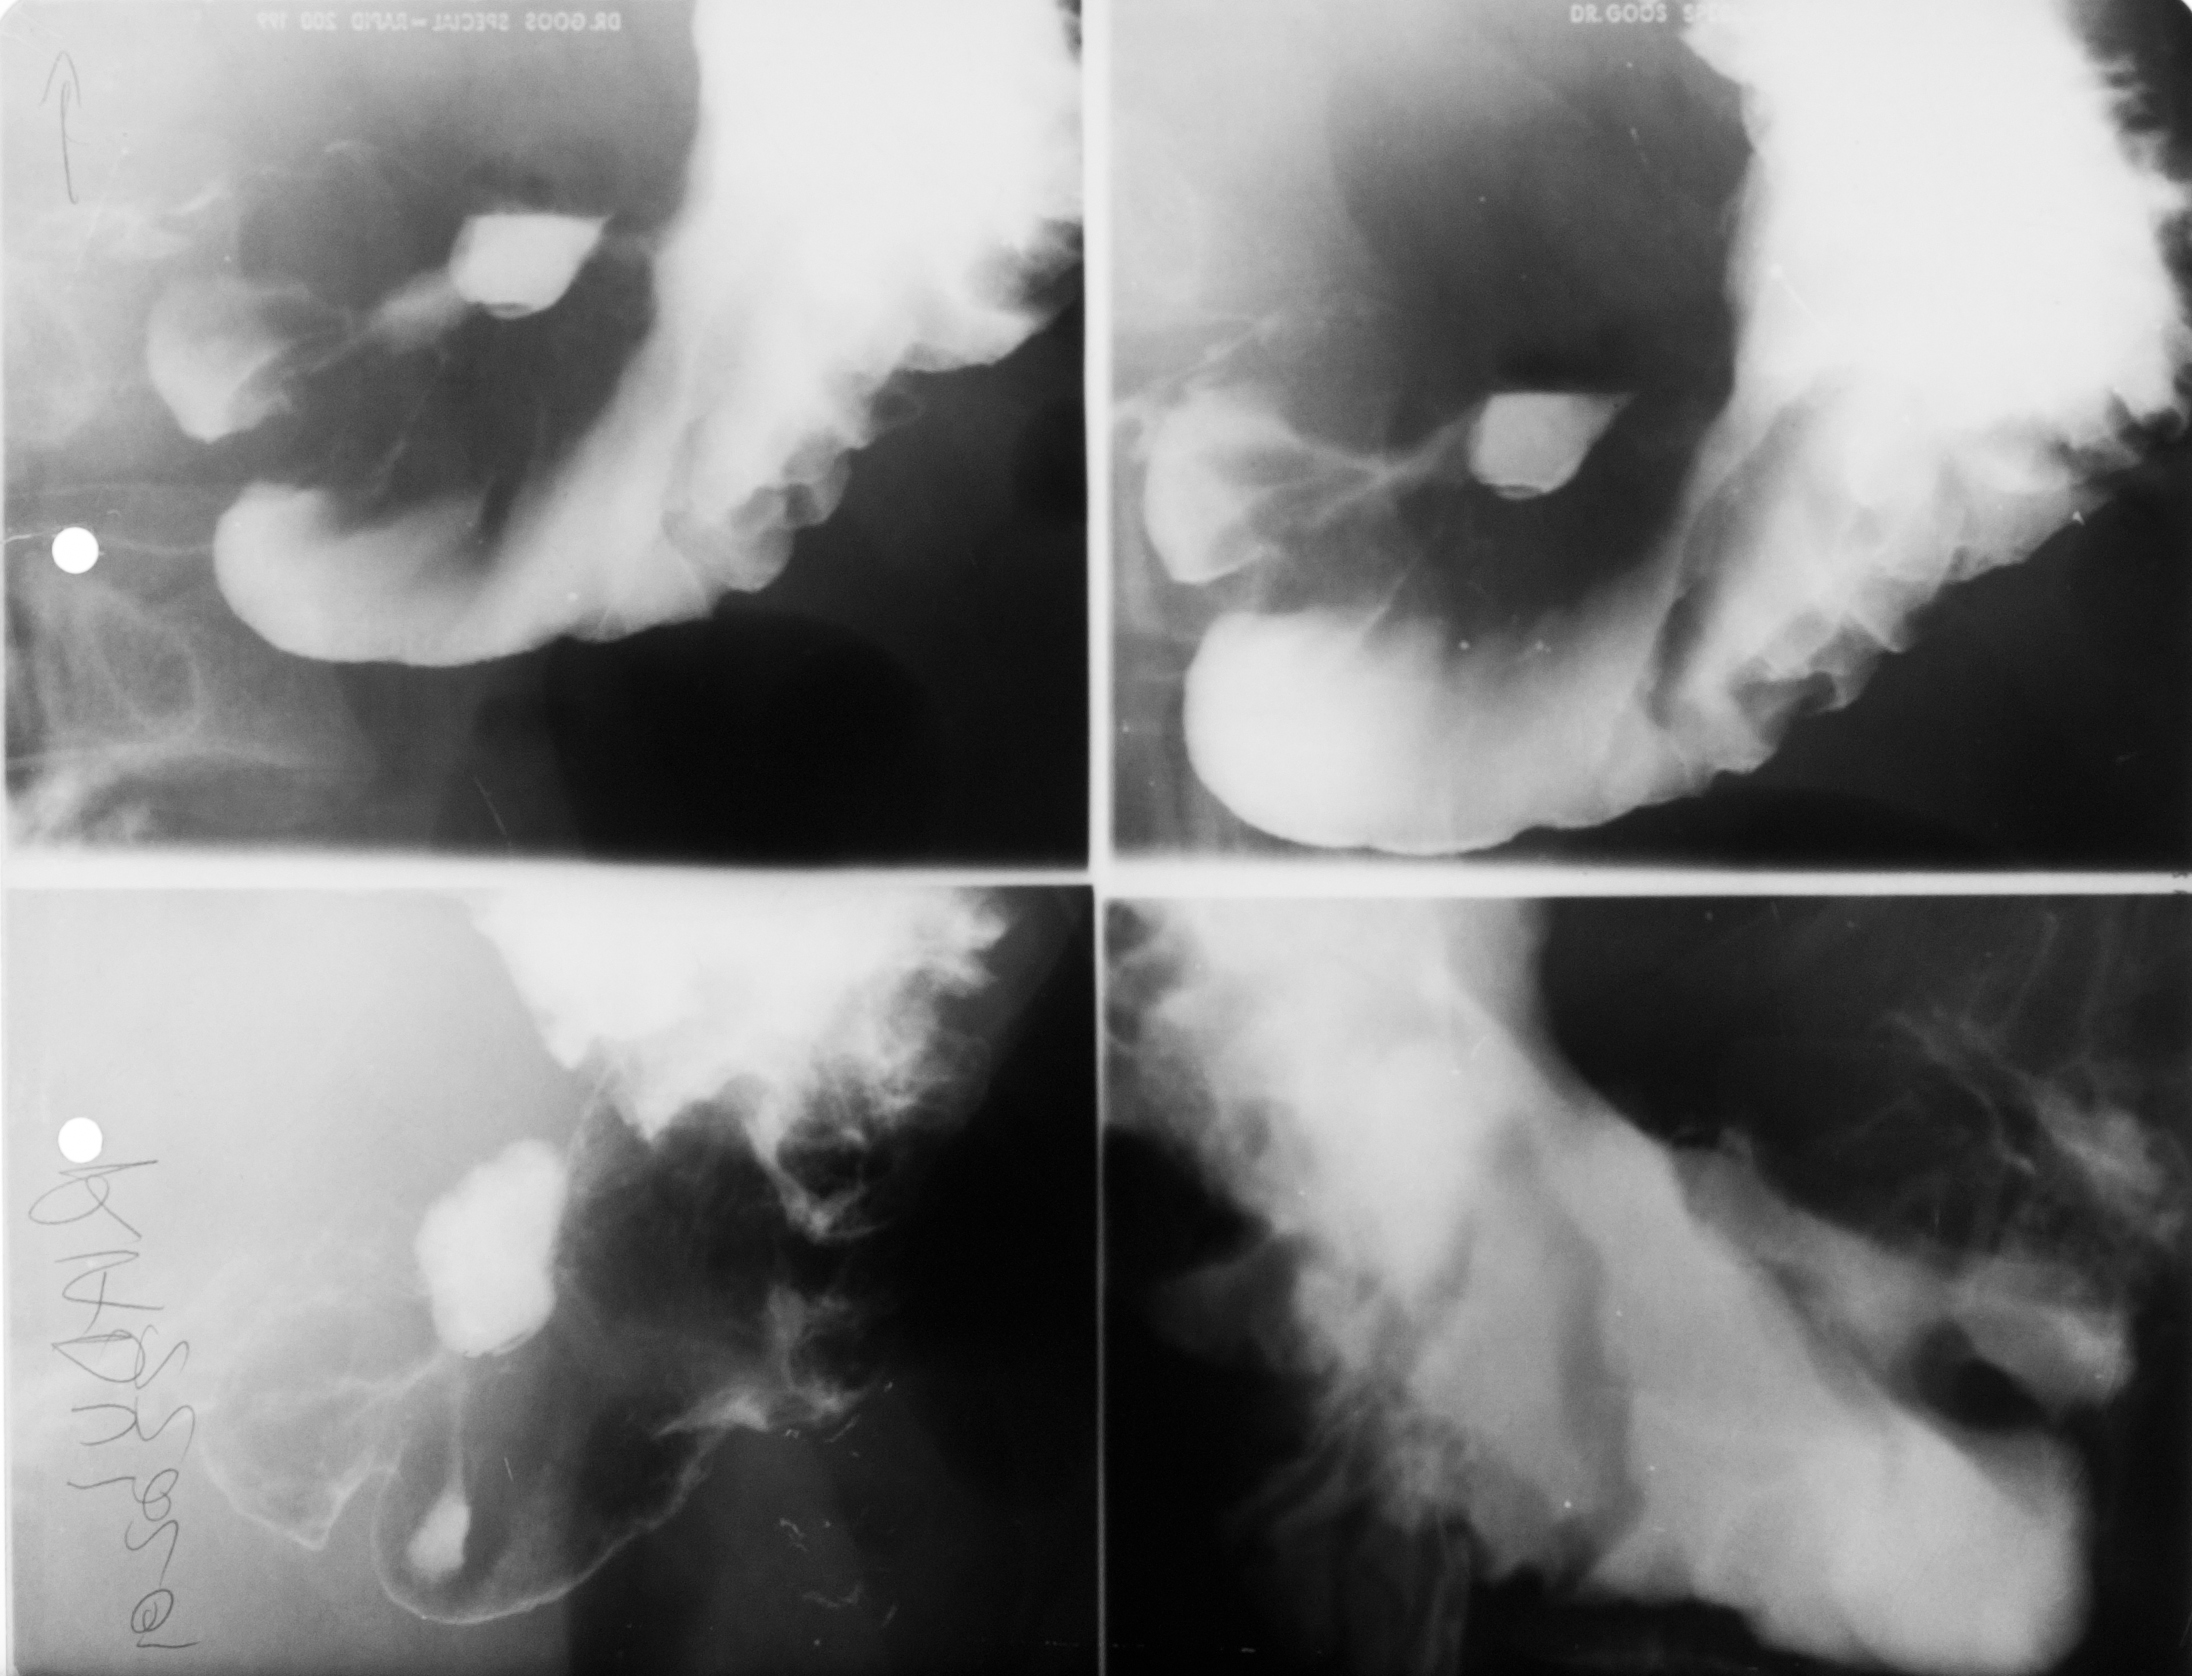

STOMAC NORMOTON(aspectul radiologic)

Tranzitul baritat al stomacului.Aspectul stomacului cu substanță de contrast:forma literei J cu fornix,corp,antru,canal piloric + bulb duodenal,D2(partea descendentă a duodenului

STOMAC ORIENTALIZAT/HIPERTON (aspect radiologic normal)

Stomacul hiperton este caracteristic persoanelor scurte și grase

STOMAC ALUNGIT (aspect radiologic normal)

Stomac alungit cu polul inferior aproape de nivelul crestei iliace.Este caracteristic persoanelor longiline

STOMAC DILATAT

Stomac destins cu substanță de contrast cu polul inferior aflat în micul bazin

Stomac dilatat cu mult lichid de secreție și stază gastrică

: NIȘA BENIGNĂ

Tranzit baritat la nivelul stomacului..La nivelul curburii mici se observă o imagine de adiție mai mult adâncă decât lată,cu pliuri de mucoasă ce converg spre zona respectivă

NIȘĂ BENIGNĂ

Nișă benignă mai mult adâncă decât lată,tot la nivelul micii curburi

ASPECT DE CLEPSIDRĂ AXIALĂ

Tranzit baritat cu aspect biloculat al corpului gastric:aspect de clepsidră axială(ceea ce înseamnă că în zona mediocorporeală se află un neoplasm infiltrativ)

ASPECT BILOCULAT AL CORPULUI GASTRIC

Tranzit baritat la nivelul corpului gastric cu incizură la nivelul curburii mari și aspect biloculat al corpului gastric:biloculare de tip benignă

Biloculare excentrică?

ASPECT BILOCULAT AL CORPULUI GASTRIC

Biloculare excentrică

NIȘĂ BENIGNĂ

Tranzit baritat la nivelul stomacului..Se observă o imagine de adiție,nișă de tip benign,mai mult adâncă decât lată

: NIȘĂ BENIGNĂ

Nișă benignă care iese din conturul gastric,mai mult adâncă decât lată

Prima imagine de la stânga:examinare în dublu contrast

A doua imagine:examinare în mono contrast

: STENOZĂ

Tranzit baritat cu stenozarea lumenului gastric la nivel corporeal și antral

Stenoză,cel mai probabil,de tip malign